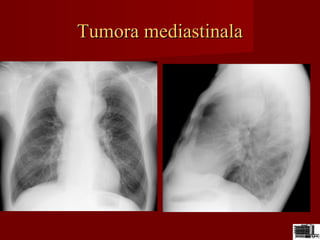

Tumora mediastinalaTumora mediastinala